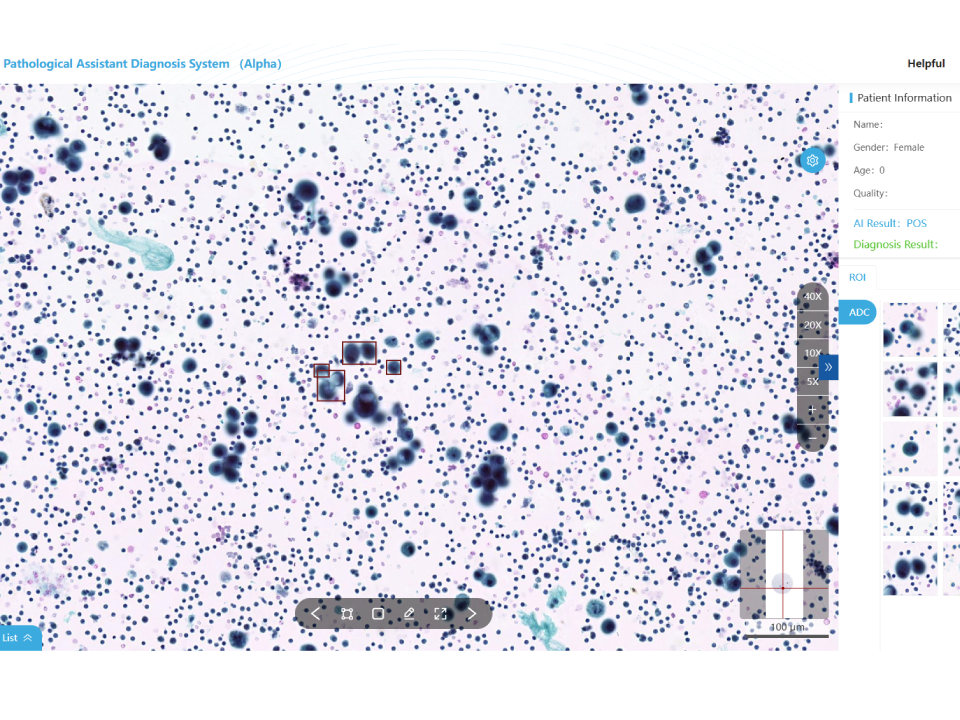

Hydrothorax and Ascites Cytology Assistant Diagnostic Module

Automatic recognition of malignant tumor cell Assist physicians with cytologic diagnosis. Whole slide analysis to reduce misdiagnosis.. Validated by multi-center clinical trials: sensitivity≥96%,specificity≥90%, Quantities 10000+ Increase the positive detection rate

Hydrothorax and Ascites Cytology Assistant Diagnostic Module

Automatic recognition of malignant tumor cell Assist physicians with cytologic diagnosis.

Whole slide analysis to reduce misdiagnosis..

Validated by multi-center clinical trials: sensitivity≥96%,specificity≥90%, Quantities 10000+

Increase the positive detection rate